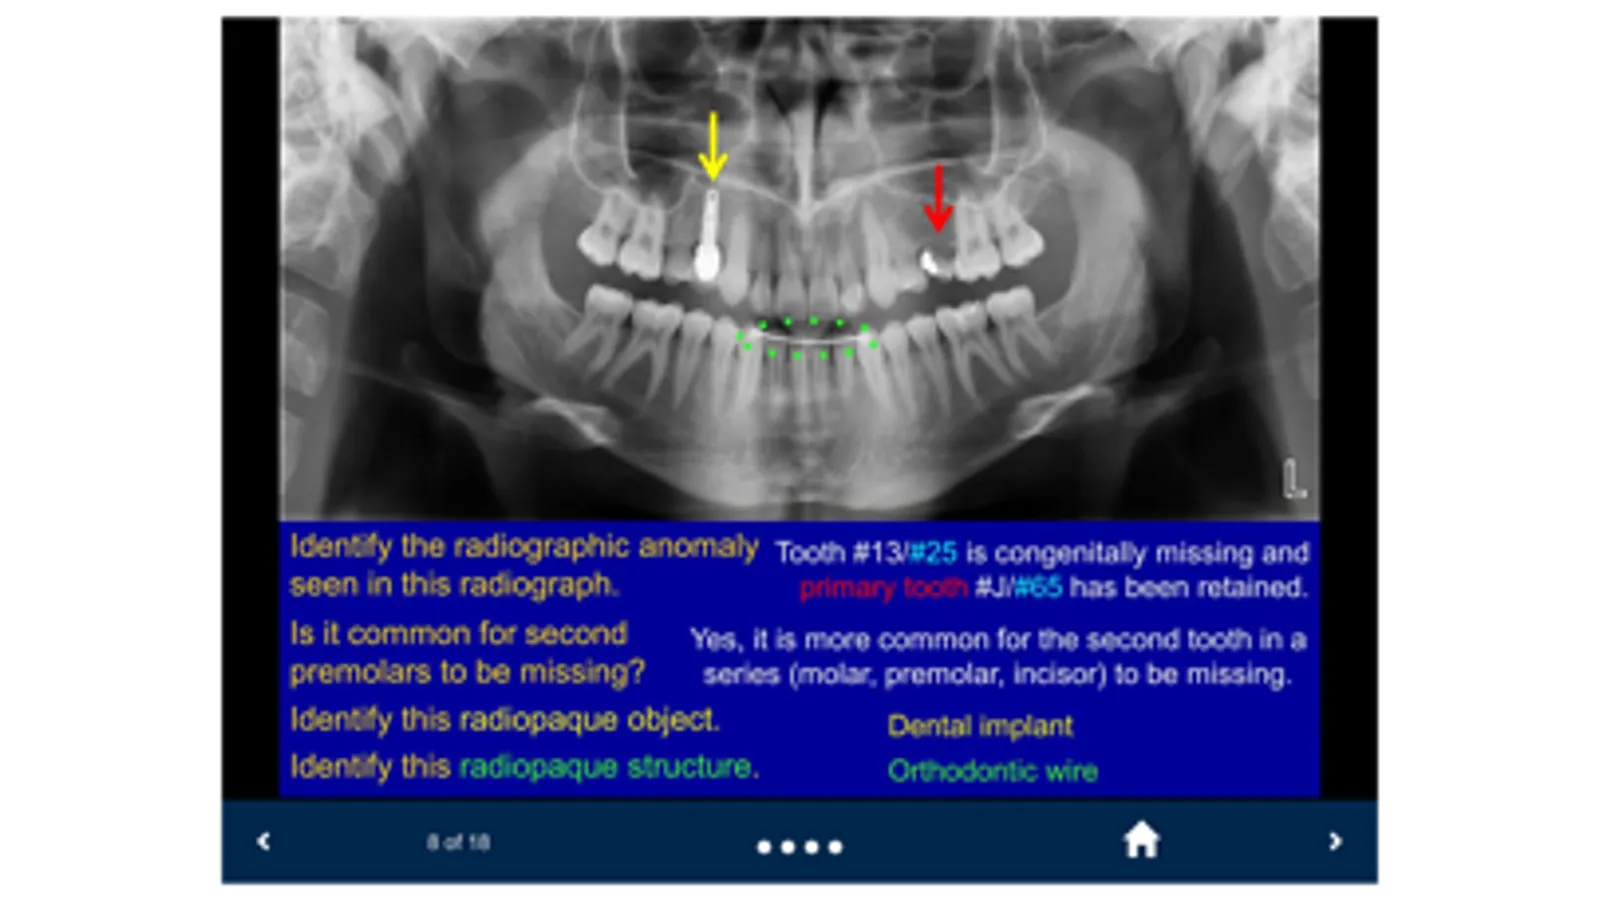

The SecondLook™ Oral Radiology mobile app will help learners of the dental sciences to self-test their level of knowledge and ability to recognize technical errors, anatomical structures, dental disease, and maxillofacial pathology in intraoral and panoramic radiographs, as well as CBCT scans. This app covers the following topics: Radiographic Anatomy (on Periapical & Bitewing Radiographs); Radiographic Anatomy (on Panoramic Radiographs); Image Quality and Common Errors; Radiographic Interpretation; Radiographic Anomalies; Buccal Object Rule (BOR); Cone Beam Computed Tomography (CBCT); Pediatric Radiology; and Presentations of Oral Pathologies (including inflammatory lesions, cyst and cyst-like lesions, benign tumors of the jaws, malignant diseases, bone and systemic diseases).